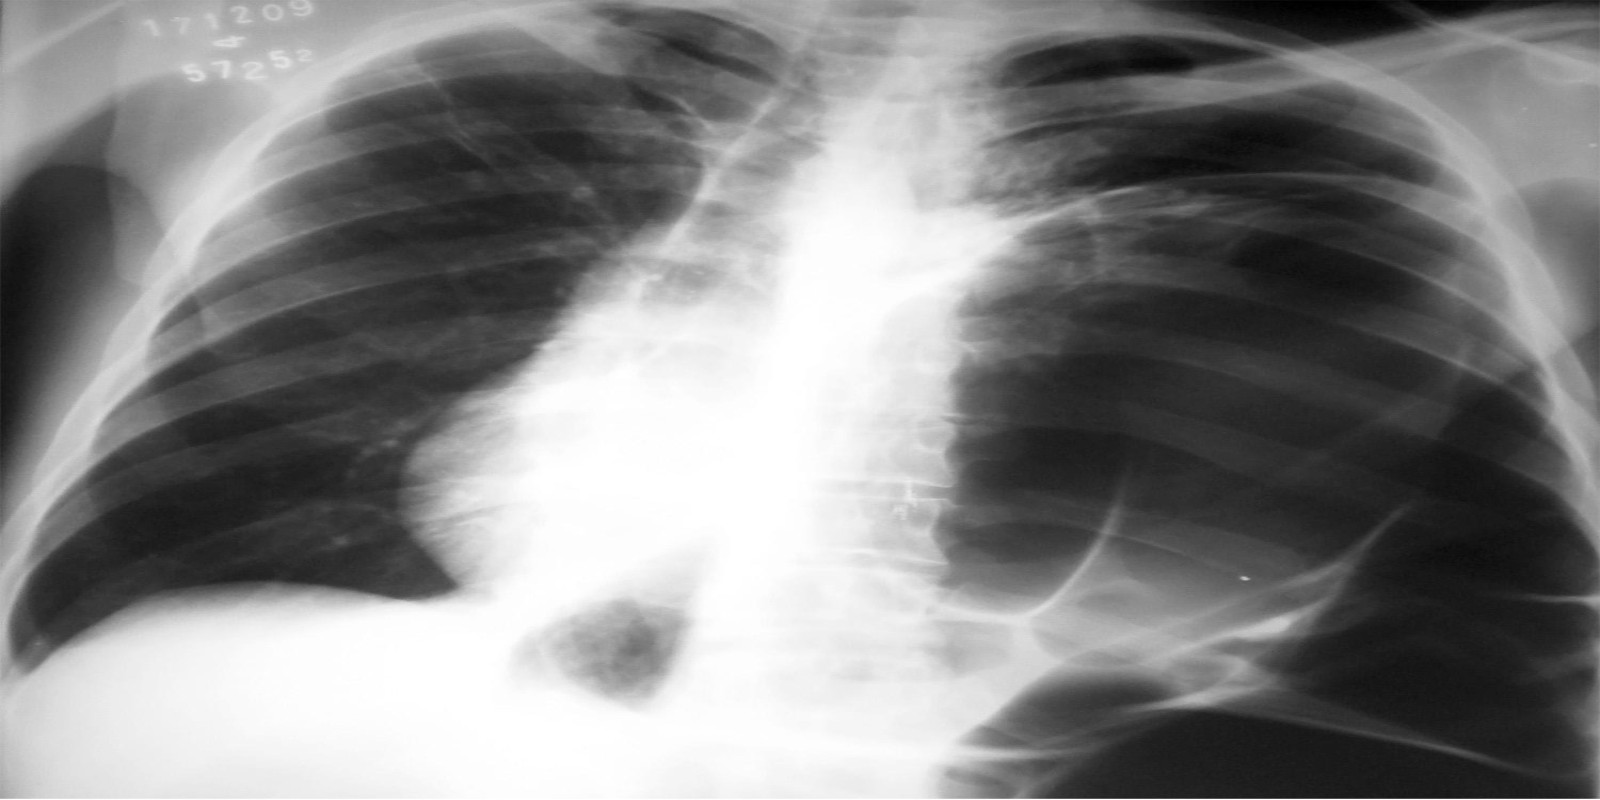

Eventração diafragmática

Diaphragmatic Eventration